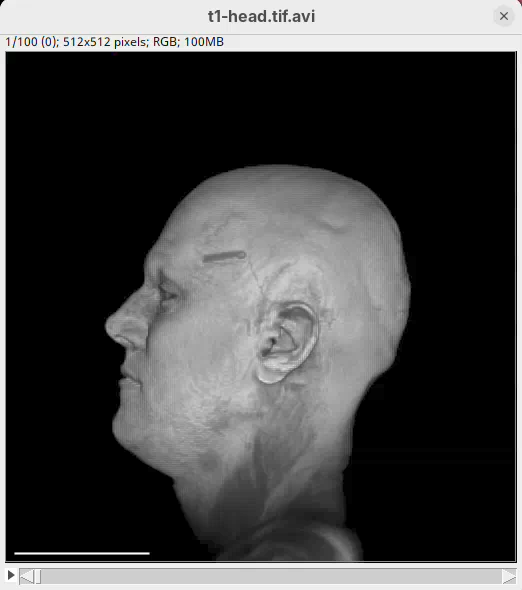

We will begin by visualizing an MRI dataset of a human head that is bundled in Fiji.

File>Open Samples>T1 Head (16-bits).

The BigDataViewer interface will open showing an optical section of the head sample.

Two new windows will open: 3D Animation with the initial rendering of the data and Interactive Raycaster with all the fields to control the rendering parameters.